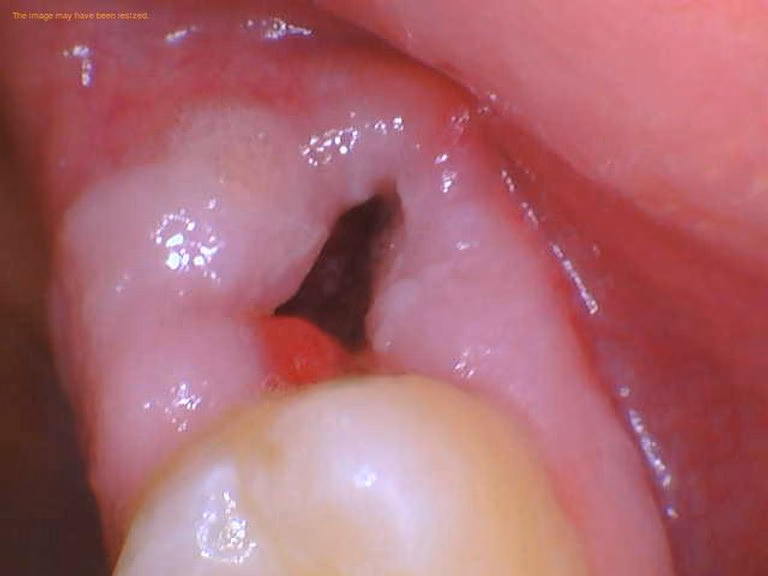

Hvad er 'dry socket' (alveolitis), og hvordan undgår jeg det?

Dry socket er en smertefuld tilstand, der opstår, når blodproppen i tandhullet forsvinder for tidligt og blotlægger knogle og nerver. Smerten er intens og stråler ofte ud i kæben. Du undgår det bedst ved at følge tandlægens anvisninger nøje: undgå rygning, sugerør og kraftig mundskylning de første dage.